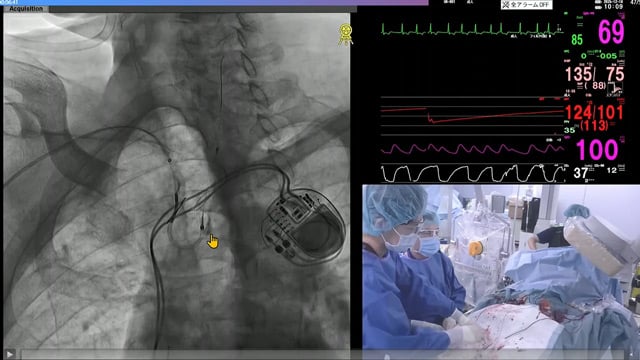

New horizons in structural heart disease therapy - Cutting-edge stroke prevention devices: WATCHMAN × SENTINEL

15 Feb 2026 – From PCR Tokyo Valves 2026

This session delves into the advances in stroke prevention for patients undergoing transcatheter aortic valve implantation (TAVI) with atrial fibrillation, focusing on left atrial appendage closure (LAAC) and cerebral protection strategies. It highlights the evolving role of WATCHMAN devices and the SENTINEL Cerebral Protection System, emphasizing...